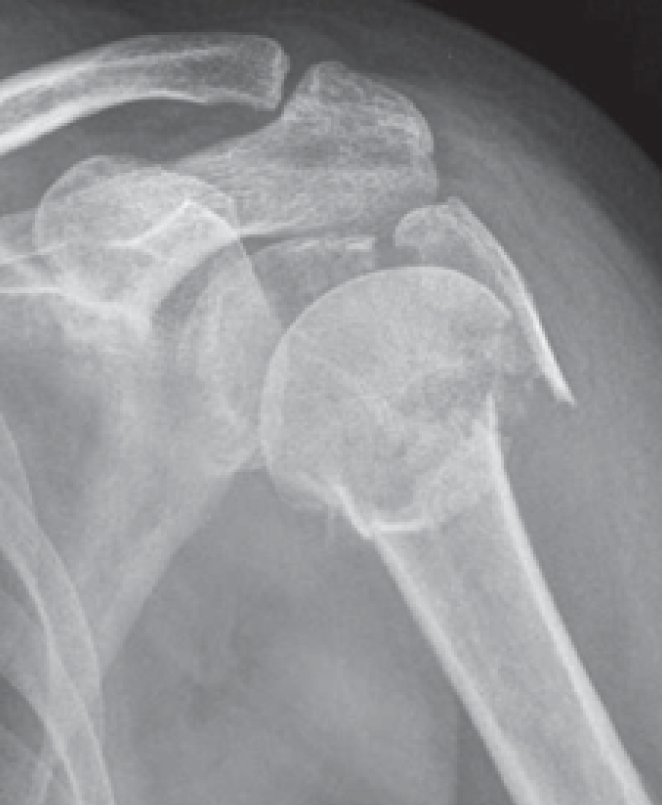

Der klassische Verschleiß des Schultergelenkes tritt im Vergleich zum Hüft- und Kniegelenk beim älteren Menschen seltener auf. Hierbei erfolgen eine Zerstörung des Gelenkknorpels und die Deformierung der Gelenkflächen, die zu einer schmerzhaften Bewegungseinschränkung des Schultergelenkes führen (Abb. 34, 37).

Verschiedene Schultergelenkserkrankungen können den Einbau eines künstlichen Schultergelenkes erforderlich machen. Der Anlass für solch einen Eingriff sind neben den sichtbaren Veränderungen des Gelenkes im Röntgenbild oder im CT die Beschwerden des Patienten, wobei in erster Linie der starke Ruhe- und Belastungsschmerz zu nennen ist, der eine mehr oder weniger regelmäßige Einnahme von Medikamenten erforderlich macht.

Schultergelenksprothesen gibt es seit über 50 Jahren. Gerade in den letzten 20 Jahren hat die Schulterendoprothetik große Fortschritte gemacht. Bei der schmerzhaften Zerstörung des Schultergelenkes durch Arthrose (Gelenkverschleiß), rheumatoide Arthritis (rheumatische Gelenkentzündung), Oberarmkopfnekrose (Absterben des Oberarmkopfes) oder Oberarmkopfbruch ist es heute mit gutem Erfolg möglich, die Gelenkflächen von Oberarmkopf und Schulterpfanne durch Prothesen aus Titan und Polyethylen zu ersetzen. Die Indikation zur Implantation einer Schultergelenksprothese wird gestellt bei: